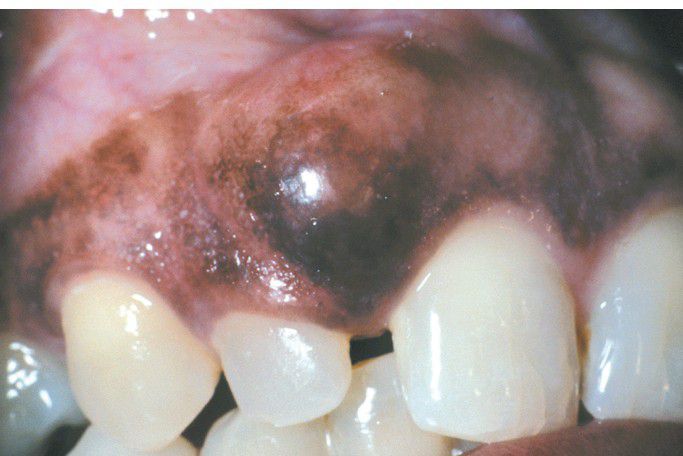

Peripheral Ameloblastoma.

Sessile gingival mass.